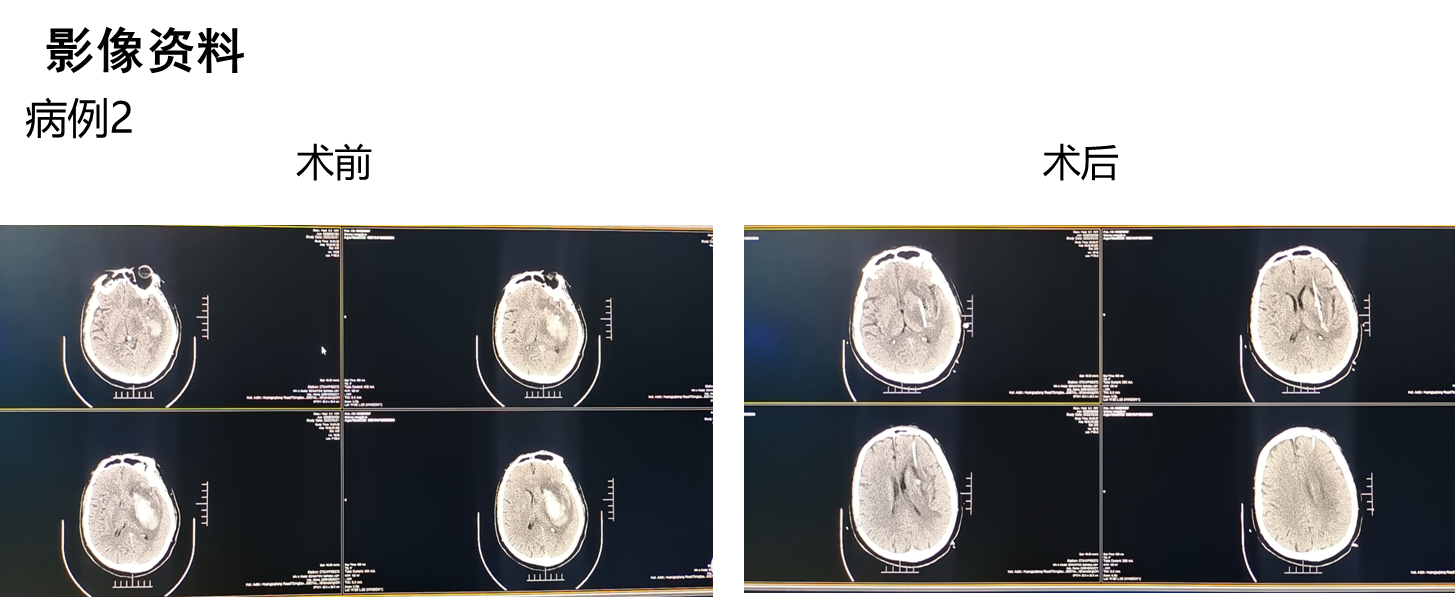

病例术前术后影像:

新型内窥镜技术可实现血肿清除手术全程可视化,包括血肿穿刺、血肿清除及血肿腔内精准电凝止血,手术切口长2.5cm,仅需单一直径1cm骨孔,镜体工作通道外径小于7mm,手术在全内镜内操作,十分微创,血肿部位的深浅在新内镜手术中无难度差别,新型内窥镜血中可视能力,不但可以在全程清晰可视下一次性清除绝大部分血肿,而且还可在有明显出血的血肿腔内轻易找到出血点并进行精准电凝止血,基于新型内窥镜所具有的颠覆性功能,有理由预判脑出血治疗的一些尚没有结论的重要问题的结果。